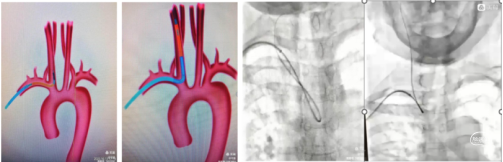

1、经桡动脉通路建设:局麻下置入右桡动脉7F薄壁桡动脉鞘。路图下在0.035in导丝及140cmsim造影导管配合下将7F远端通路导引导管在造影导管引导下到达右侧颈总动脉远端建立通路。下图1

2.置入保护装置:微导丝引入5mm保护伞,路图下将保护伞释放于该侧颈动脉岩骨段近端。下图2、3

3.球囊预扩张:

沿保护伞的微导丝将4mm×30mm球囊置于狭窄段,路图下以工作压缓慢扩张,造影显示狭窄较前改善,退出球囊。

4、支架植入:

沿保护伞导丝置入9mm×40mm Wallstent

支架,下图1、2。支架跨越狭窄段开放良好,残余狭窄,下图3。沿保护伞的微导丝将4mm×30mm球囊置于狭窄段行后扩张一次,回收保护伞,下图4。

1、通路建立:

因右侧髂动脉闭塞,经左侧股动脉穿刺不顺利。改行右侧上肢桡动脉置入5F动脉鞘,主动脉弓造影后置入泥鳅导丝交换为6FNeuron MAX长鞘。

130Cm Sim2导管超选右侧颈总动脉后将泥鳅导丝跟进至颈总动脉远端。沿130CmSim2导管将6FNeuron MAX长鞘送至颈总动脉近分叉部。

2、置入保护装置:微导丝携带2.0Ⅹ12mm冠脉球囊扩张狭窄部位,下图1。置入5.0mm保护伞于颈内动脉C1段狭窄以远,下图2。

4、植入支架:撤出球囊,沿保护伞导丝输送7一10一40mm自膨支架,铆定狭窄部位。固定支架推送杆不下移,缓慢释放支架。造影显示支架位置良好,沿保护伞导丝送入单弯造影导管回收保护伞于体外造影显示:支架位置良好,残余狭窄不明显。